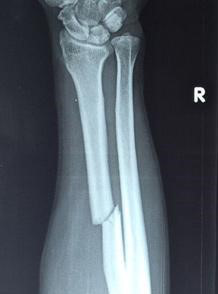

1,局部血液供应:如果骨折部血液供应好,则骨折愈合快,如肱骨的外科颈(上端)骨折;反之,局部血液供应差者,骨折愈合慢,如股骨颈骨折。骨折类型也和血液供应有关:如螺旋形或斜形骨折,由于骨折部分与周围组织接触面大,因而有较大的毛细血管分布区域供应血液,愈合较横形骨折快。

2,骨折断端的状态:骨折断端对位不好或断端之间有软组织嵌塞等都会使愈合延缓甚至不能接合。此外,如果骨组织损伤过重(如粉碎性骨折),尤其骨膜破坏过多时,则骨的再生也较困难。骨折局部如出血过多,血肿巨大,不但影响断面的接触,且血肿机化时间的延长也影响骨折愈合。